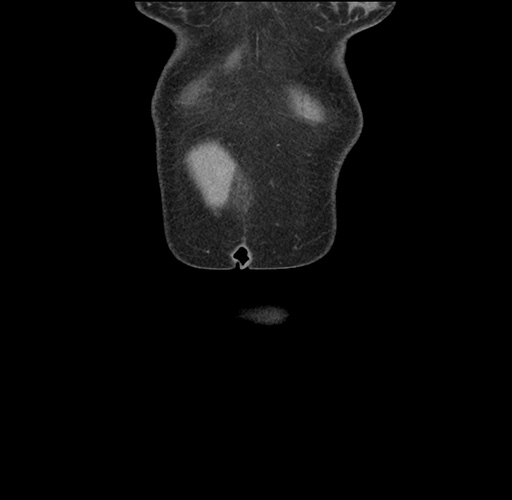

Imaging Analysis

Look through the patient's CT scan to identify any areas of concern for the necessary procedure.

Based on your CT findings, which issue(s) would give reason for "planned slowing down moment(s)" in this case?